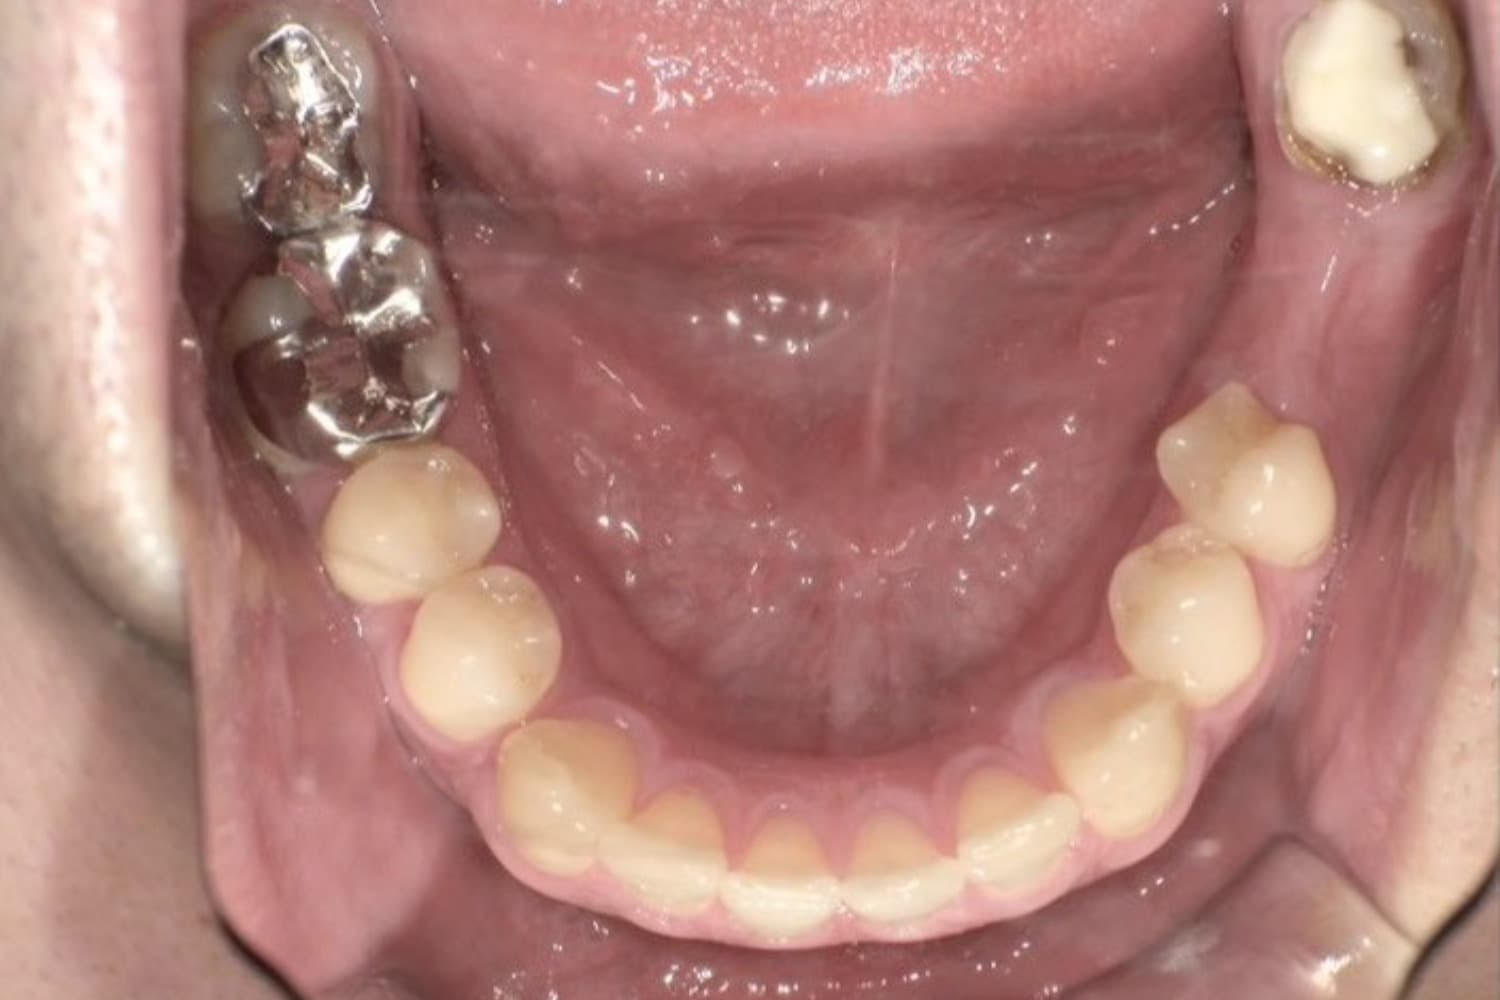

Before

下顎全てをオールオン4で治療

50代

男性

入れ歯が合わなくて痛い。固定式のインプラントで美味しくご飯を食べられるようにして欲しい。

6ヶ月〜8ヶ月

8回

合計:220万円(税込み242万円) インプラント4本(インプラント本体) : 20万円×4本=80万円(税込み88万円) 上部構造::ジルコニアクラウン×12本=140万円(税込み154万円)

・手術後には腫れや痛みが生じる可能性があります。 ・インプラント診療は自由診療となります。 ・治療後、慣れるまでは一定期間噛むと違和感が生じることがあります。 ・歯磨きにコツが必要なので、歯磨きの練習が必要。